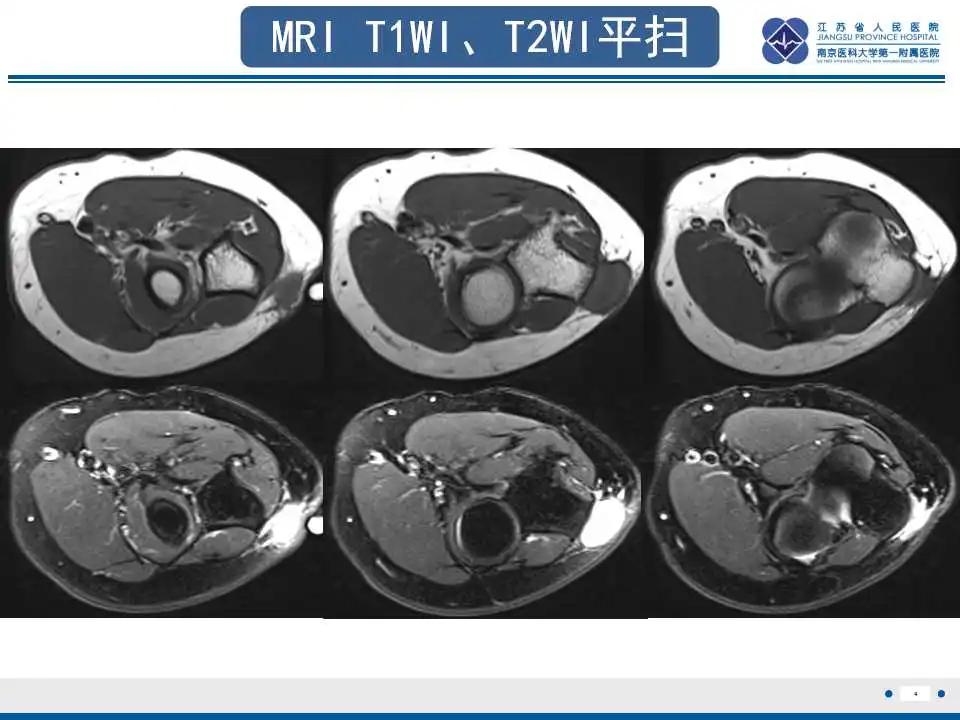

MRI检查揭示结节性筋膜炎独特影像

MRI在显示结节性筋膜炎的细节方面具有优势。在T1加权图像上,病变通常表现为等信号或略高信号。而在T2加权图像上,病变则呈现高信号或稍高信号。增强后,病灶会明显强化,这种强化模式与CT增强类似。